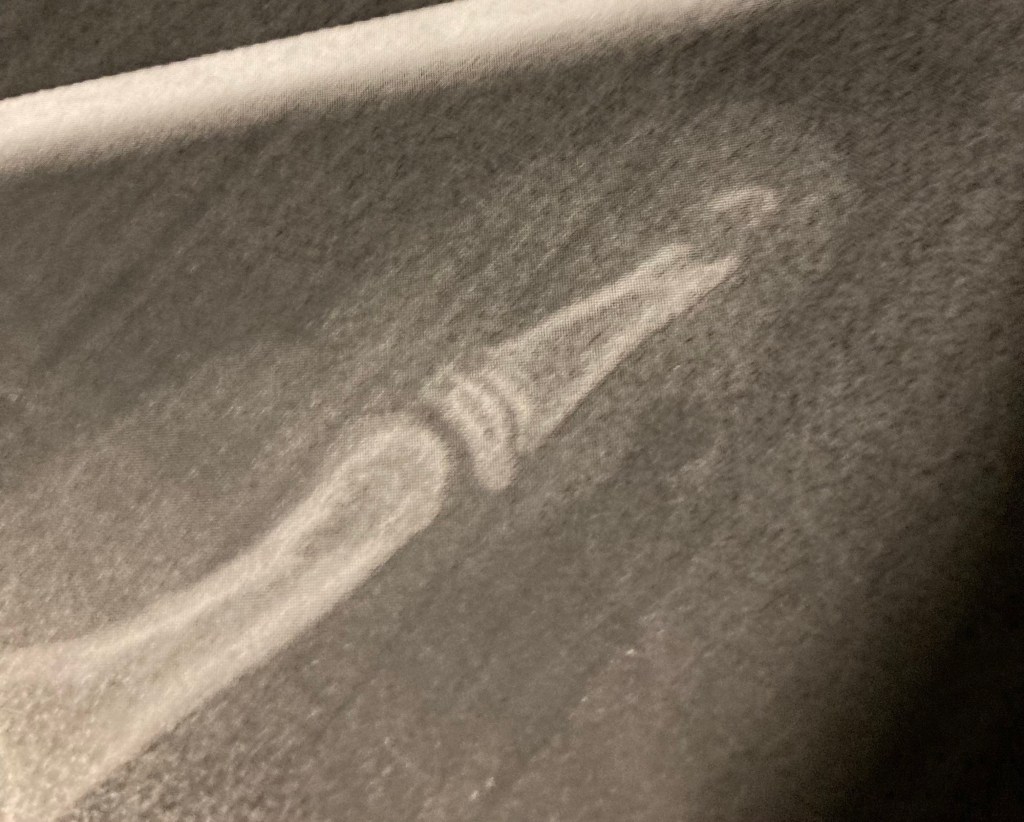

[KM:] „Ganz okay, aber es hat ein bisschen geblutet.“

[folienstern:] „Naja, das war ja auch ziemlich doll gequetscht und gebrochen. Und ich wusste nicht, dass man Fingernägel annähen kann! Und Löcher in den Nagel bohren, damit es sich nicht staut….“